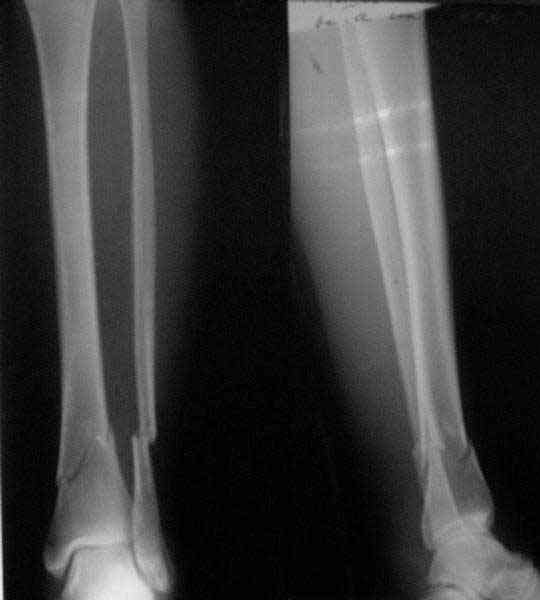

A typical case is attached, also an image with intra-op reduction obtained by a small wire distractor, in the moment of insertion a Poller wire in AP direction. Fixation by a SIGN nail. Despite the fibula was not fixed healing was obtained with the unchanged alignment.

There are some more tricks which allow not to plate the fibula and provide good alignment and stability. A small wire distractor can provide alignment and restore length of both tibia and

fibula. Angular stability of the tibia is provided by insertion of more than two conventional medial-lateral locking screws. To maintain the position of the fibula perQ insertion of a single position screw often could be enough. I bet the articles didn't analyze the options.